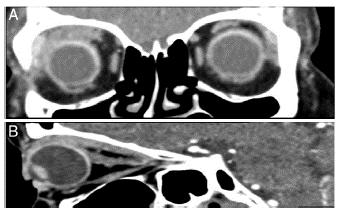

Mujer de 56 anos que en 2013 comenzó con dolor y proptosis ocular derecha, fue tratada con esteroides sistémicos, con lo cual el episodio remitió. En 2015 nuevamente presentó dolor y proptosis ocular derecha, fue atendida por el oftalmólogo quien documentó por tomografía axial computarizada (TAC) de órbitas, miositis extraocular; con la finalidad de obtener diagnóstico fue sometida a biopsia de músculo recto superior y glándula lagrimal. El resultado histopatológico fue inflamación inespecífica (fig. A1 y A2); recibió prednisona a dosis de 1mg/kg/día por 2 meses con lo que remitió. En marzo de 2016 presentó pérdida de peso, fiebre, dolor neuropático en extremidades inferiores, proptosis ocular derecha dolorosa; mediante TAC se documentó miositis extraocular (fig. 2A y 2B). Se integró el diagnóstico de GPA por la afectación ocular, síntomas constitucionales, neuropatía sensitiva en extremidades inferiores y anticuerpos contra citoplasma de neutrófilos (ANCA) positivos, (c-ANCA: 1:40 [valor de referencia: <1:40] y PR3: 5,4 [valor de referencia: <4,3]). Recibió 3 bolos de metilprednisolona de 1 g y ciclofosfamida 1 g de forma mensual durante 6 meses; posteriormente se realizó TAC de órbitas en noviembre de 2016 (fig. 3A y 3B) en la cual se encontró remisión de la manifestación ocular.

Figura 2 A) TAC de órbitas con reconstrucción sagital derecha en donde se observa discreto aumento en el grosor del músculo recto superior, el músculo recto inferior de características conservadas. B) TAC de órbitas con reconstrucción coronal en donde se observa engrosamiento de músculos recto superior y lateral de órbita derecha con discreto desplazamiento caudal del globo ocular.